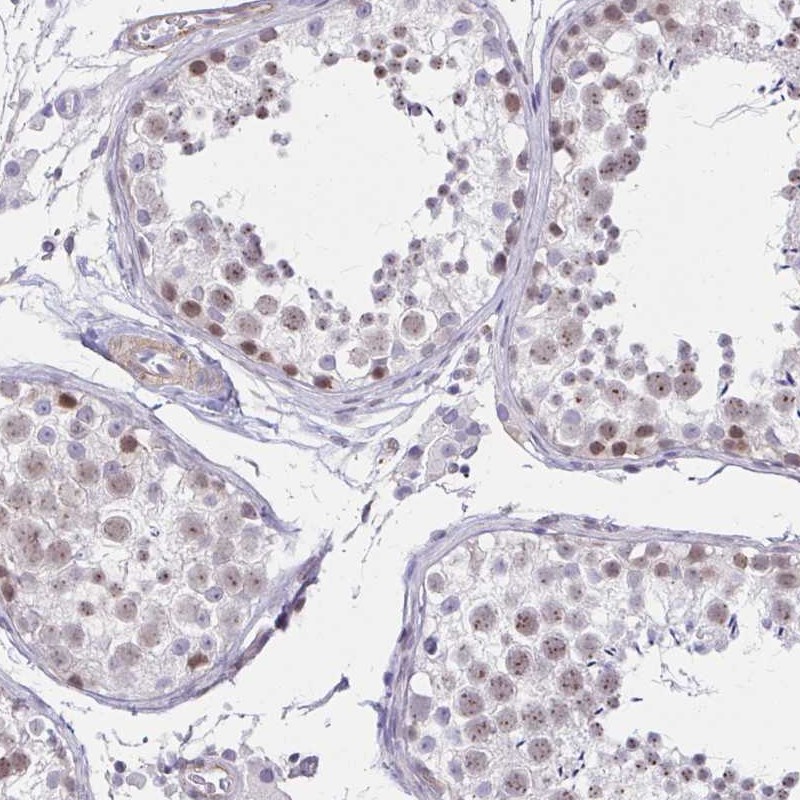

Immunohistochemical staining of human testis shows moderate nuclear positivity in cells in seminiferous ducts.